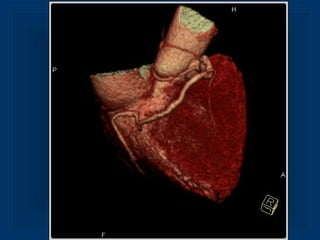

Maximum Intensity Projection RCA 3D VRT LCX and RCA

Maximum Intensity ProjectionRCA 3D VRT LCX and RCA